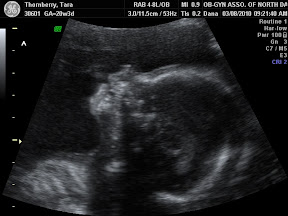

Today was the 'big scan'. It was so amazing. Seeing not only the girl's hearts beat, but seeing the four chambers of each of their hearts beating beautifully. The technician measured around their little noggins and their tummies. She measured the length of their legs and arms. We got to see their adorable little feet as well as their kidneys and stomachs. The technician even surprised us with a 4d picture of each of them. They're just beautiful. They've apparently already started sucking on their thumbs and playing footsie with one another. Baby A was especially active starting out head down, kicking her sister in the head, and then flipping over so that they were both feet down.

Here are some of the pictures from today's visit:

Baby A 4D:

Baby B 4D: